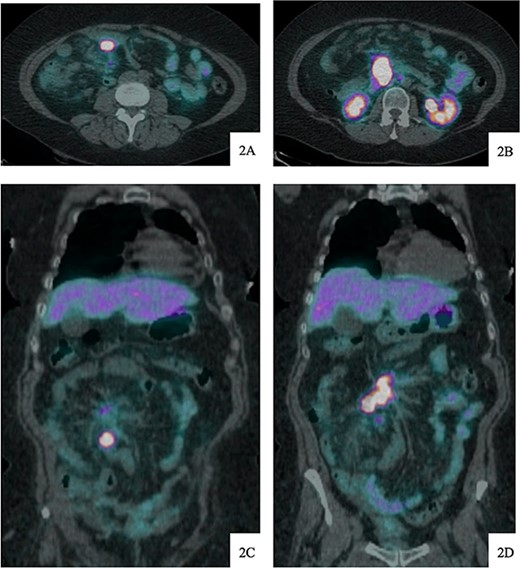

DOTATATE positron emission tomography-computed tomography scan revealing extent of metastatic disease.